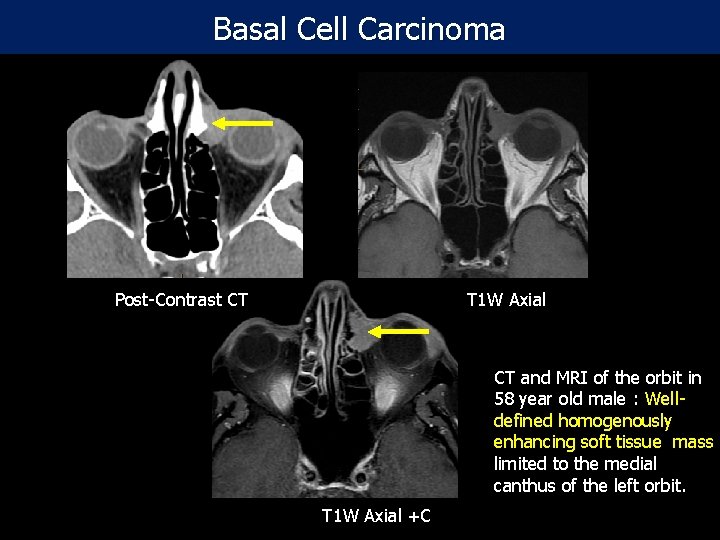

Basal Cell Carcinoma Post-Contrast CT T 1 W Axial CT and MRI of the orbit in 58 year old male : Welldefined homogenously enhancing soft tissue mass limited to the medial canthus of the left orbit. T 1 W Axial +C